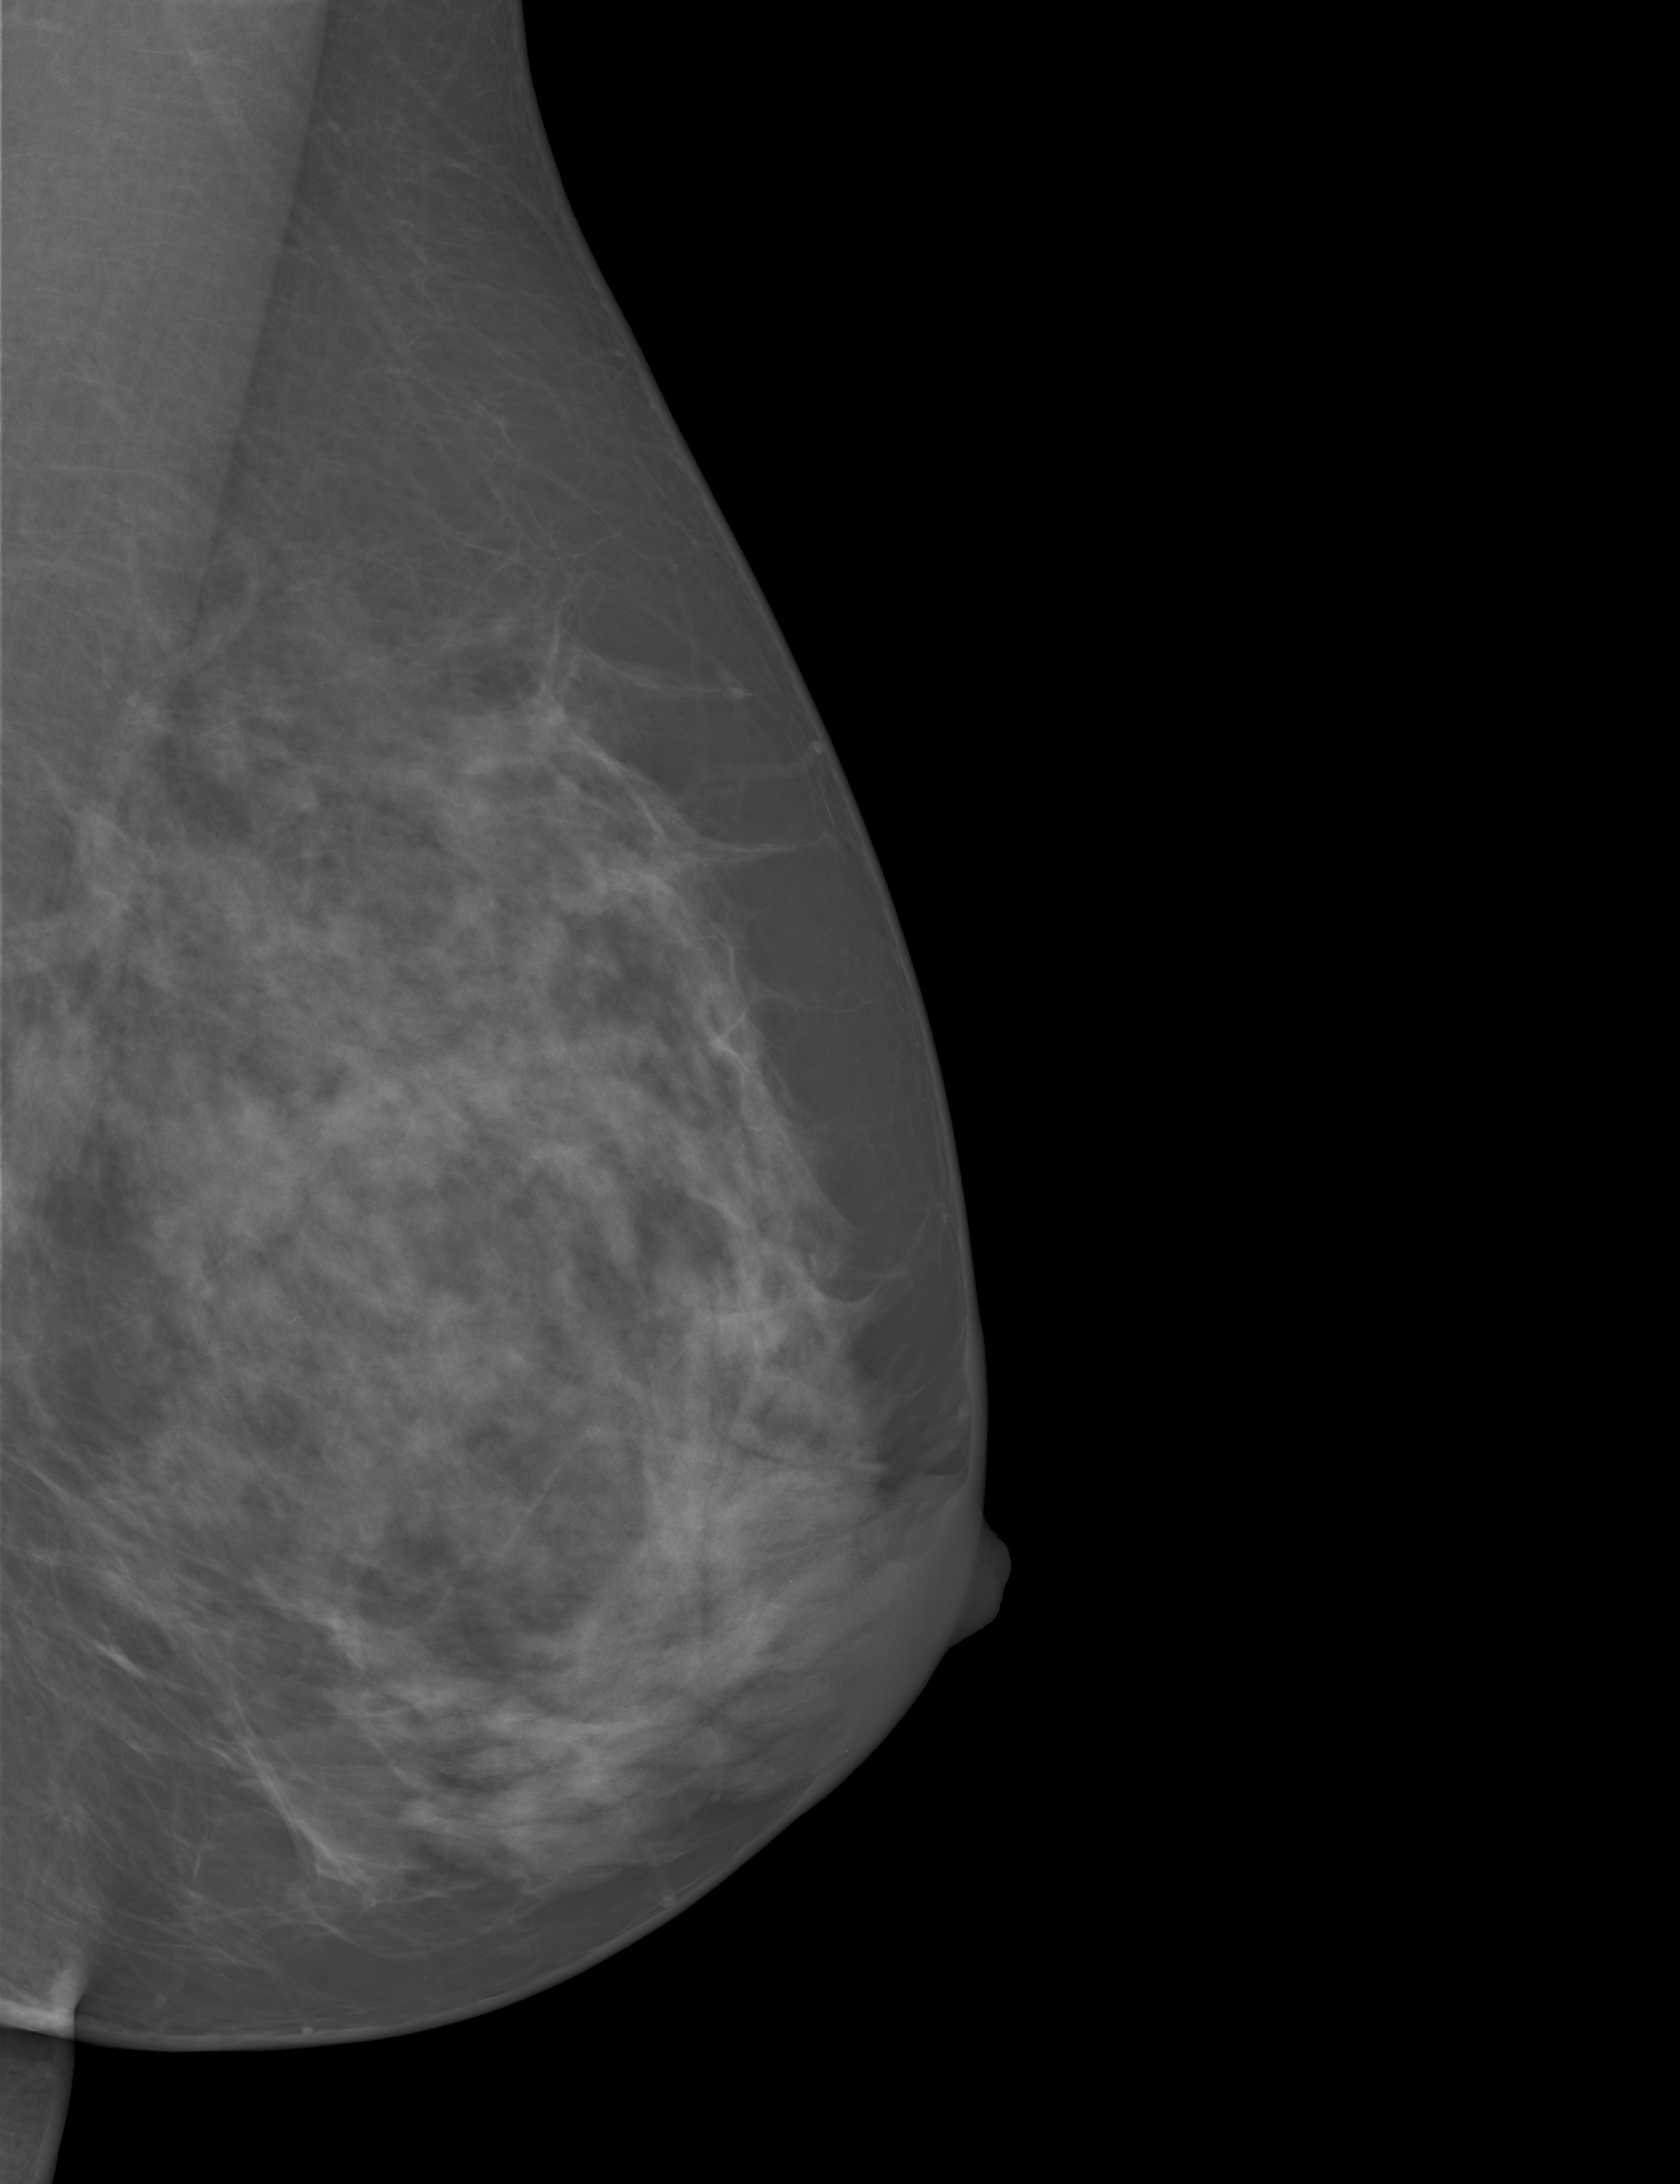

In this study, we evaluated our methods on the public available dataset, INbreast dataset[21], which contains 115 cases (410 images). Among the 115 cases, 90 cases are from women with both breasts affected (4 images per case) and 25 cases are from mastectomy patients (2 images per case). Two views for each breast were recorded, a craniocaudal (CC) view, which is a top to bottom view, and a mediolateral oblique (MLO) view, which is a side view. The dataset provides a breast density assessment of each mammograph with the corresponding labels of BI-RADS categories, which makes it suitable for our study. The mammographs were acquired on x-ray films and saved by the standard Digital Imaging and Communications in Medical (DICOM) format. The image matrix has either 3328×4084332840843328\times 4084 or 2560×3328256033282560\times 3328 pixels. Among the 409 images(1 missing the label), 136 are classified as BI-RADS I, 146 as BI-RADS II, 99 as BI-RADS III and 28 as class BI-RADS IV (example images of four categories are shown in Fig 1).

Figure 1: Example of mammographs of the different BI-RADS categories. (a) BI-RADS I, (b) BI-RADS II, (c) BI-RADS III, and (d) BI-RADS IV.